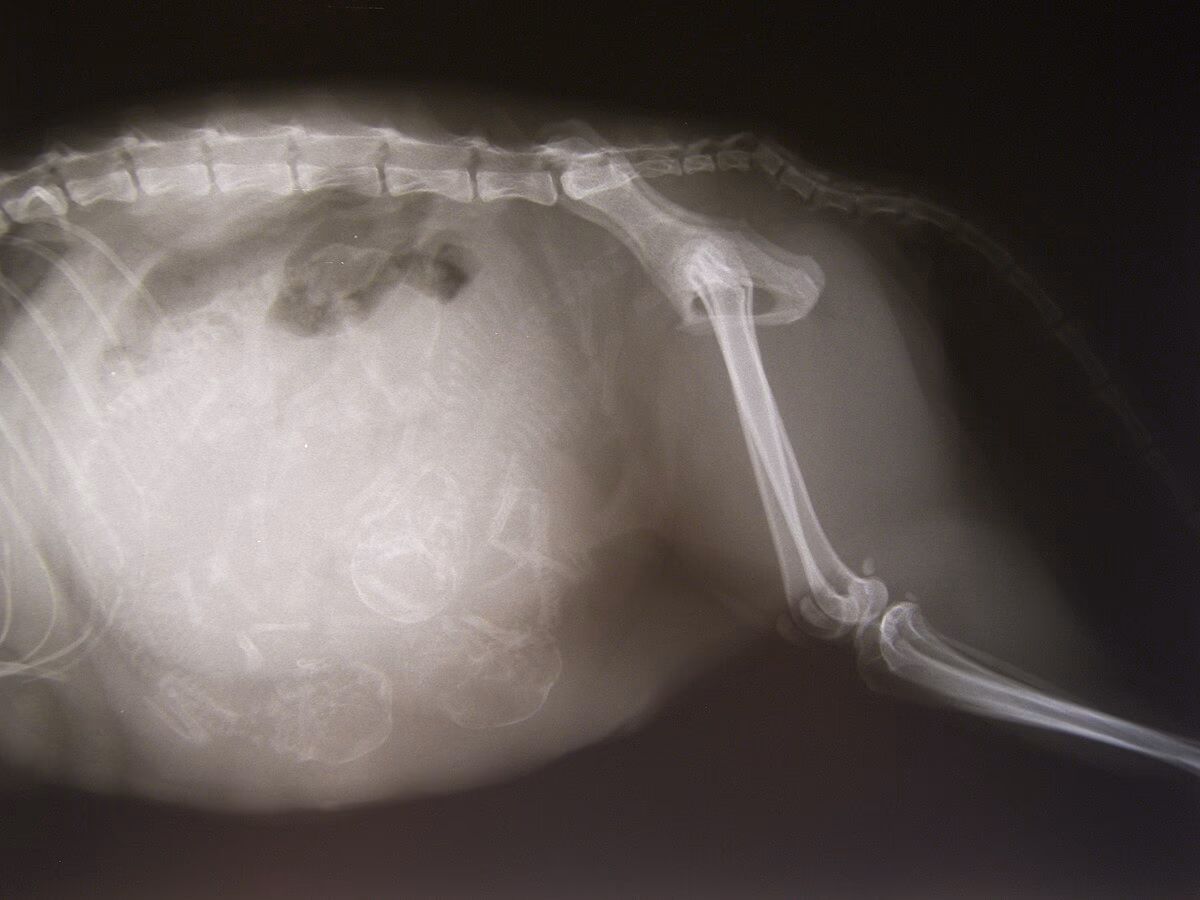

In the biological context, gestation refers to the period of development of a foetus within the uterus of a female mammal, from conception until birth. This complex and vital process is a cornerstone of reproduction, ensuring the survival and development of offspring. The duration of gestation varies significantly across species, reflecting evolutionary adaptations and differing reproductive strategies. For instance, the gestation period for a mouse is around 19-21 days, while that of an elephant can last up to 22 months. Humans typically have a gestation period of approximately 40 weeks, often referred to as the 'term' of pregnancy.